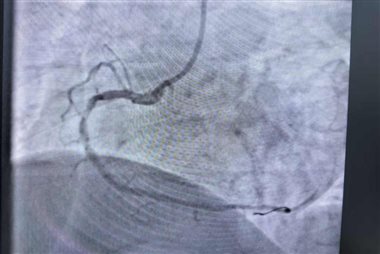

介入团队立即启动导管室。冠状动脉造影结果显示:患者右冠状动脉中段及远段95%以上狭窄,病情极为危重。医护团队紧密协作,迅速将导丝通过闭塞病变,经球囊扩张后,在病变处成功植入支架一枚,使患者心肌血液供应得以恢复,闭塞血管达到理想的TIMI血流3级状态。整个手术仅耗时30余分钟,术后患者症状显著缓解,生命体征平稳。